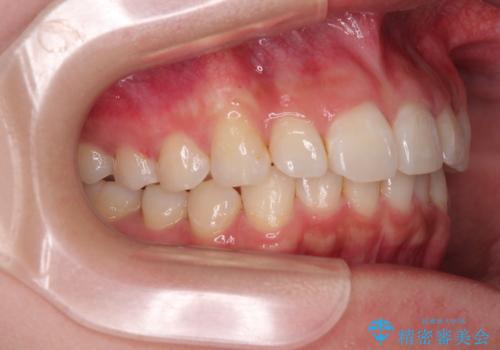

前歯の捻れを改善するとともに、口元が少しでも引っ込むように治療計画を立て、仕上げることができました。

長時間の装着を徹底し、遠方からの通院にもかかわらずしっかりと通院いただき、予想よりも早く治療を終えることができました。